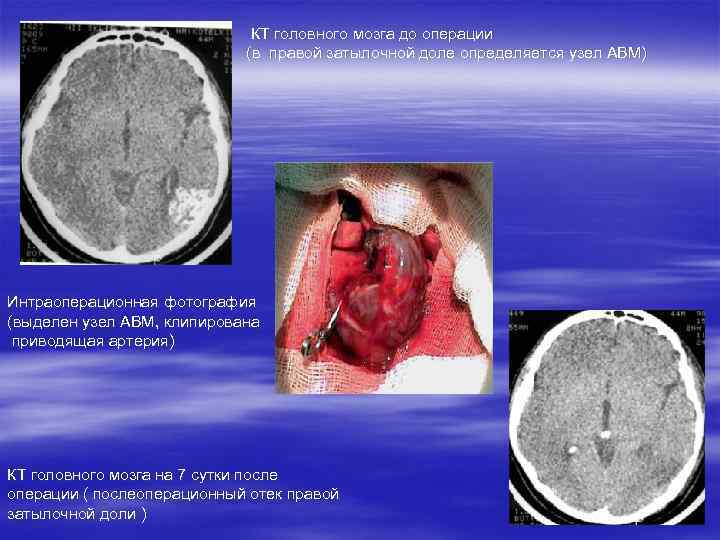

КТ головного мозга до операции (в правой затылочной доле определяется узел АВМ) Интраоперационная фотография (выделен узел АВМ, клипирована приводящая артерия) КТ головного мозга на 7 сутки после операции ( послеоперационный отек правой затылочной доли )